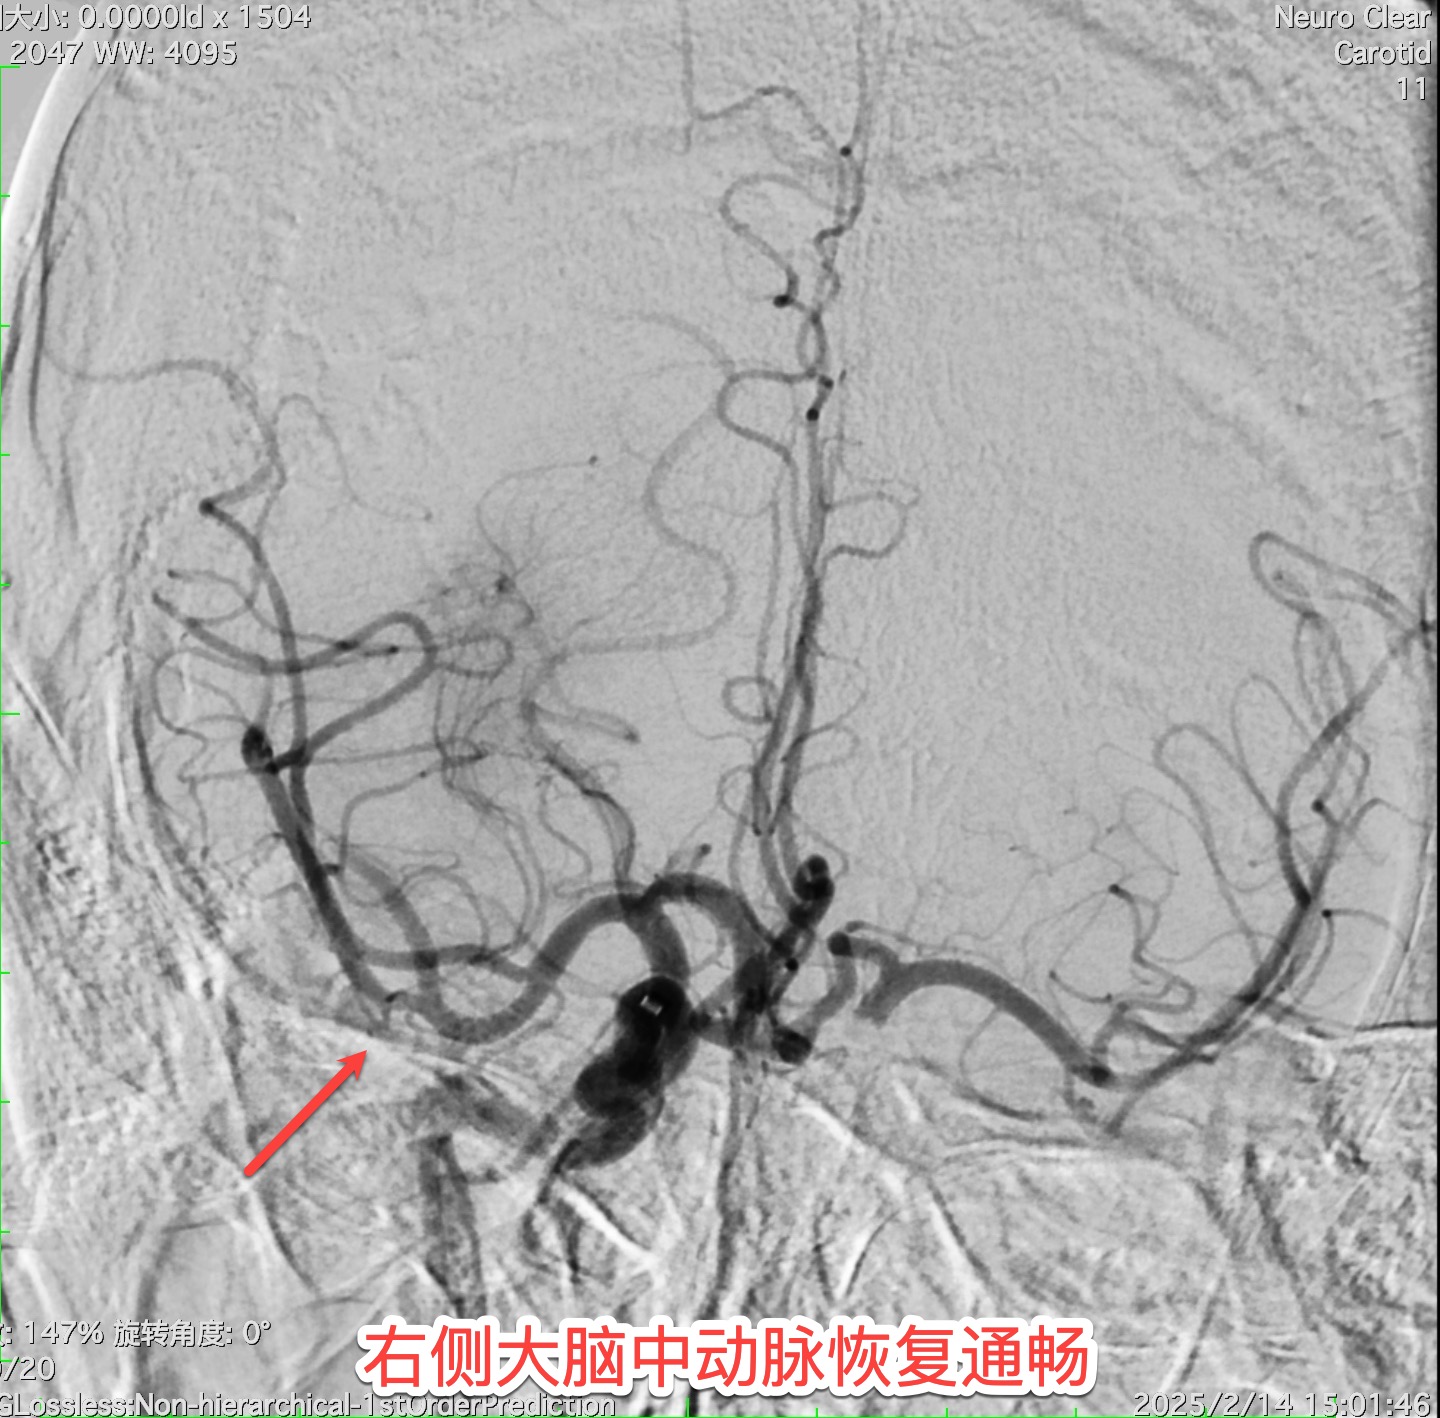

14:27,患者被推入导管室。介入科副主任医师王宁带领团队在DSA引导下精准穿刺,造影显示右侧大脑中动脉完全闭塞。“找到‘罪犯血管’了!”取栓支架如微型“捕网”般穿越重重血管,15:01,一条团块状暗红色血栓被完整取出,血流瞬间复通!从入院到血管再通,仅耗时3小时。